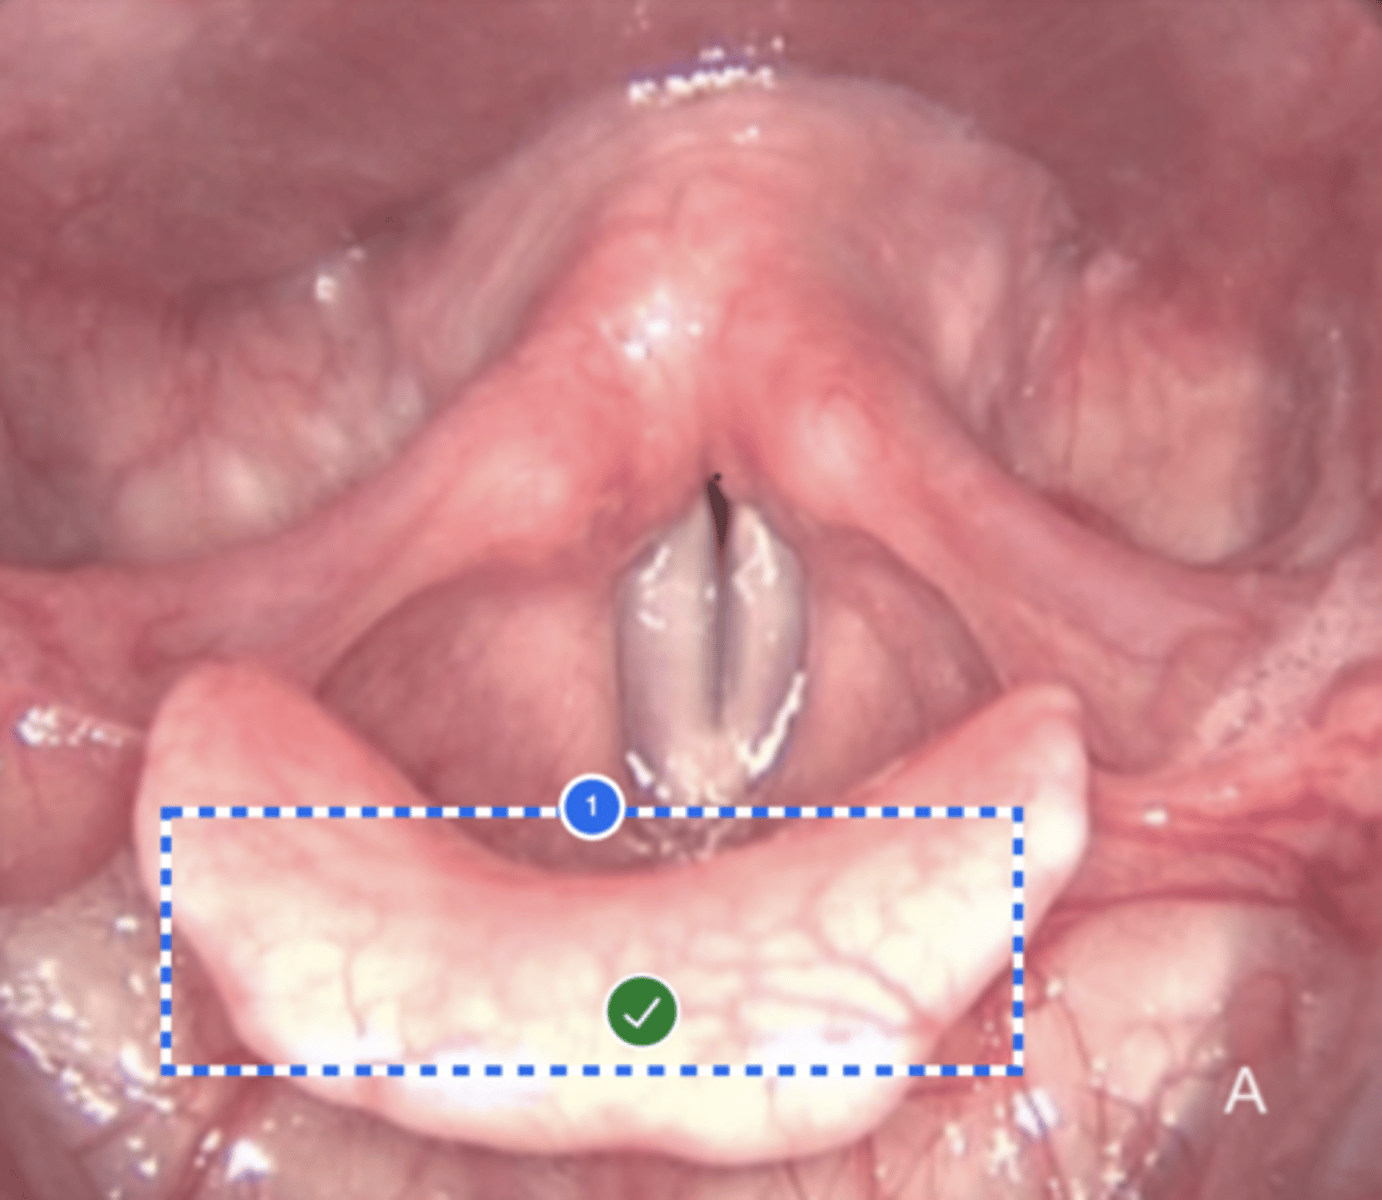

Label Laryngeal surface of epiglottis (superior view)

Label (Right) Lateral pharyngeal wall (superior view)

Label Base of tongue (superior view)

Label left vallecula (superior view)

Label Posterior Pharyngeal Wall